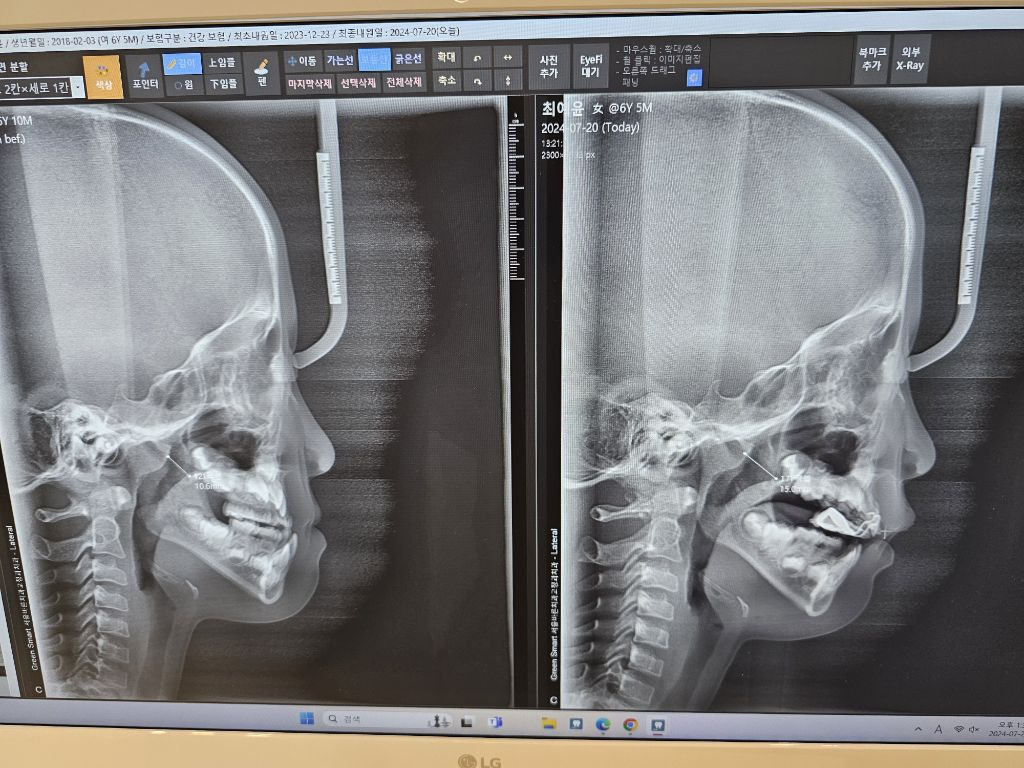

내새끼2 자랑이다대문자IxxP어린 나이이 만 5세에 교정시작해서 6개월동안 고생해서 교정이 끝났다 2차성장기때 또 하겠지만 울 애기 장하다ㅠ추천수0비추천등록된 샷 리스트교정성장기애기댓글 0댓글 정렬방식 선택추천순선택됨작성순댓글 쓰기프로필만 있으면 누구나 댓글 작성이 가능합니다.Loading...Loading...Loading...Loading...Loading...